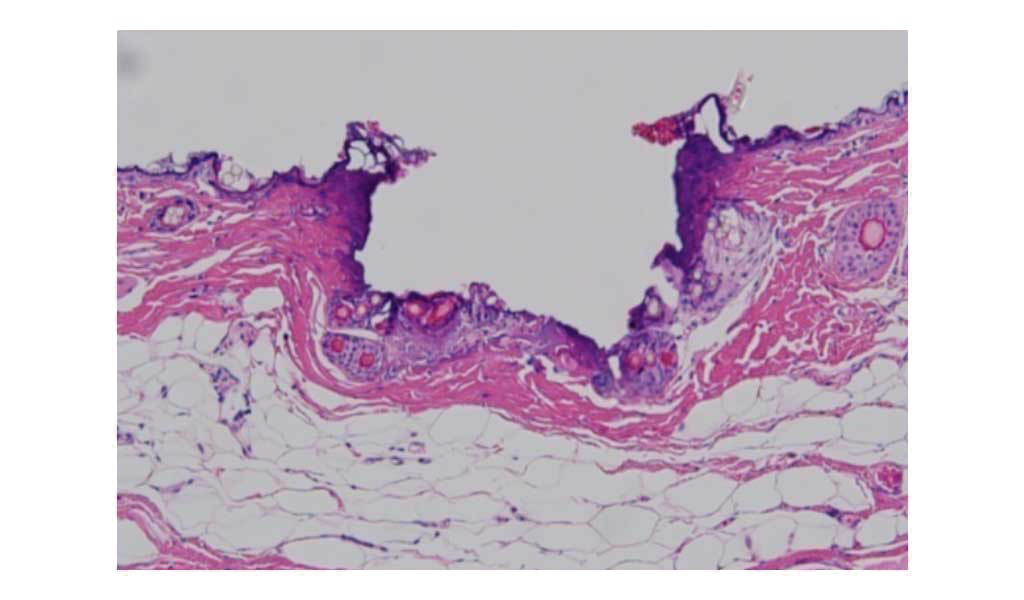

ActionⅡ(2,940nm)とモザイク(1,550nm)の違い

ActionⅡ(AFL)

約0.3mmの微細な孔蒸散されている皮膚組織

MOSAIC(Non-AFL)

微細に凝固されてた皮膚組織